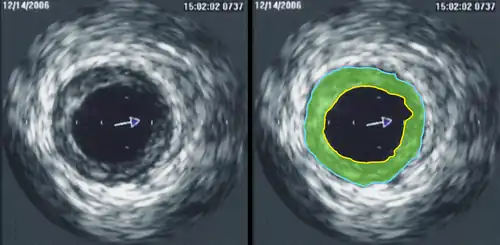

Intravascular ultrasound

Intravascular ultrasound (IVUS) is a specialized form of echocardiography that uses a catheter to insert the ultrasound probe inside blood vessels. This is commonly used to measure the size of blood vessels and to measure the internal diameter of the blood vessel. For example, this can be used in a coronary angiogram to assess the narrowing of the coronary artery. If the catheter is retraced in a controlled manner, then an internal map can be generated to see the contour of the vessel and its branches.